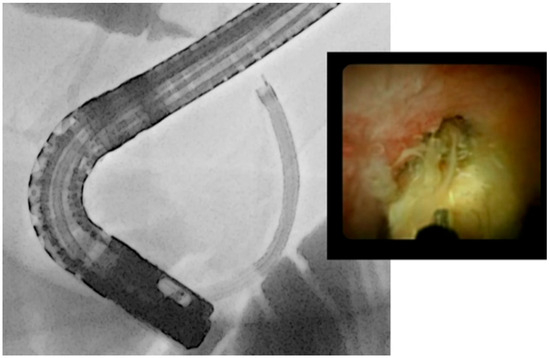

- Kamiyama, R.; Ogura, T.; Okuda, A.; Miyano, A.; Nishioka, N.; Imanishi, M.; Takagi, W.; Higuchi, K. Electrohydraulic Lithotripsy for Difficult Bile Duct Stones under Endoscopic Retrograde Cholangiopancreatography and Peroral Transluminal Cholangioscopy Guidance. Gut Liver 2018, 12, 457–462. [Google Scholar] [CrossRef]

- Oh, C.H.; Dong, S.H. Recent advances in the management of difficult bile-duct stones: A focus on single-operator cholangioscopy-guided lithotripsy. Korean J. Intern. Med. 2021, 36, 235–246. [Google Scholar] [CrossRef]